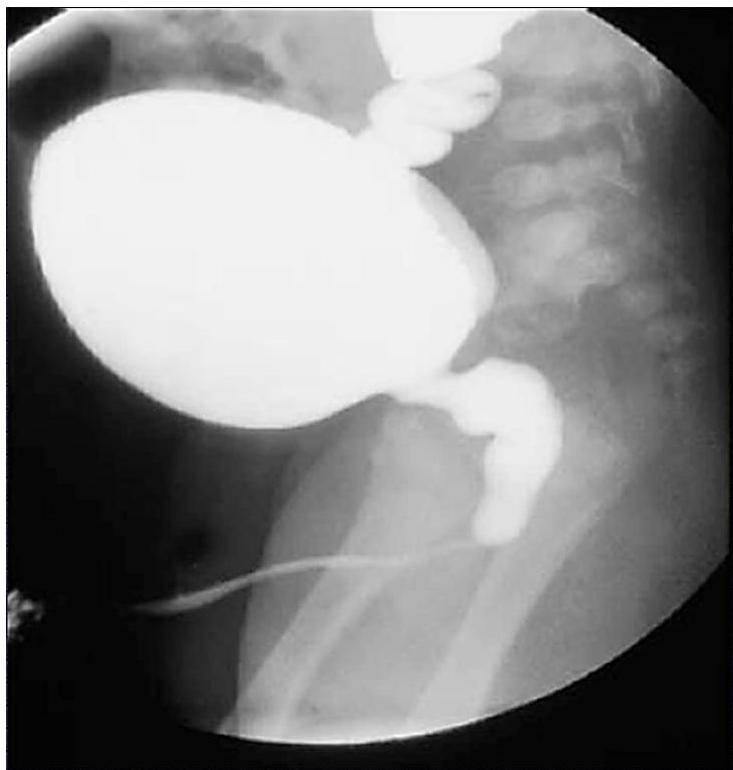

Posterior Urethral Valve (PUV)

Modality:

- MCUG / VCUG (voiding cystourethrogram) only in boys

Findings:

- Dilated proximal urethra

- Dilated ureter

- Dilated bladder

- Dilated posterior urethra

Can be diagnosed antenatal and prevented!

Complications:

- Renal failure

- UTI

Treatment:

- Surgical removal of the valve

- Catheter or drain procedure as temporary measure